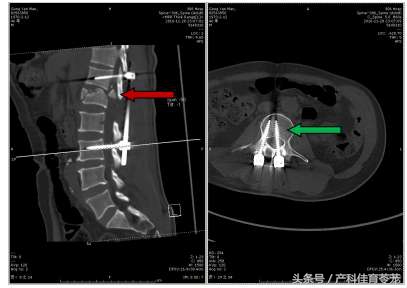

手术选择了错误的减压位置和固定节段,既没有解除神经压迫,也没有有效固定脊柱骨折(红箭为骨折椎体)。

CT可见骨折块仍位于椎管内(红箭),脊髓受压严重;更不幸的是腰3左侧螺钉植入椎管内,加重了神经损伤(绿箭)。